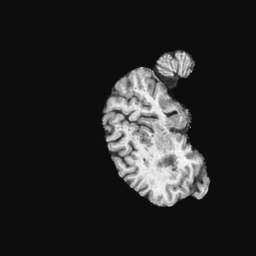

Exp. 1: Segmented adult brain data is used to evaluate our network’s regression performance with known ground truth Tisubscript𝑇𝑖T_{i}. 85 brains from the ADNI data set[1] were randomly selected; 70 brains for ΩtrainsubscriptΩ𝑡𝑟𝑎𝑖𝑛\Omega_{train} and 15 brains for ΩvalidationsubscriptΩ𝑣𝑎𝑙𝑖𝑑𝑎𝑡𝑖𝑜𝑛\Omega_{validation}. Fig. 2 shows an example slice of the ground truth and the reconstructed ΩΩ\Omega.

Figure 2: Example slice from the segmented adult brain MRI data set (a); reconstruction from 300 ωisubscript𝜔𝑖\omega_{i} based on SVRNet regression without SVR (b); SVR initialised with SVRNet predictions after eight iterations of SVR (c). Note that SVRNet (b) predicts individual slice transformations only from image intensities without any initial world co-ordinates of the sampled slice. (d) shows the achieved PSNR in dB when comparing the volumes of (b) and (c) to (a).

Reconstructing from Ti^^subscript𝑇𝑖\hat{T_{i}} initialisation without SVR yields a PSNR of 23.7 ±plus-or-minus\pm 1.09; with subsequent SVR the PSNR increases to 29.5±plus-or-minus\pm2.43 when tested on 15 randomly selected test volumes after four iterations of SVR.